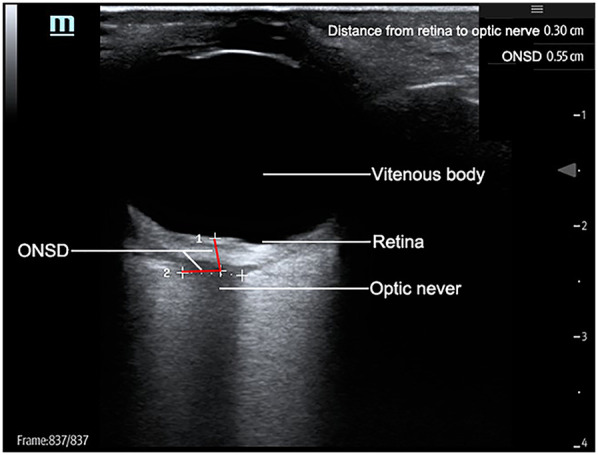

Purpose: Assessing the Clinical Value of Optic Nerve Sheath Diameter (ONSD) Ultrasonography in Pediatric Severe Intracranial Hypertension Monitoring and Treatment Efficacy Evaluation.

Methods: This study included 86 critically ill children with intracranial hypertension, and used bedside ultrasound to dynamically monitor the diameter of the optic ONSD to evaluate the status of intracranial hypertension. The experimental group (n = 33) underwent three daily ONSD ultrasound monitoring throughout the treatment process, with a baseline value of >5.2 mm set as the intervention threshold based on the guidelines of the American Society for Neurocritical Care; The control group (n = 53) was monitored using traditional clinical signs. The efficacy evaluation was conducted using the National Institute of Health Stroke Scale (NIHSS), and core indicators such as the duration of neurological function recovery, Intensive Care Unit (ICU) hospitalization period, and incidence of complications were comprehensively compared between the two groups of children.